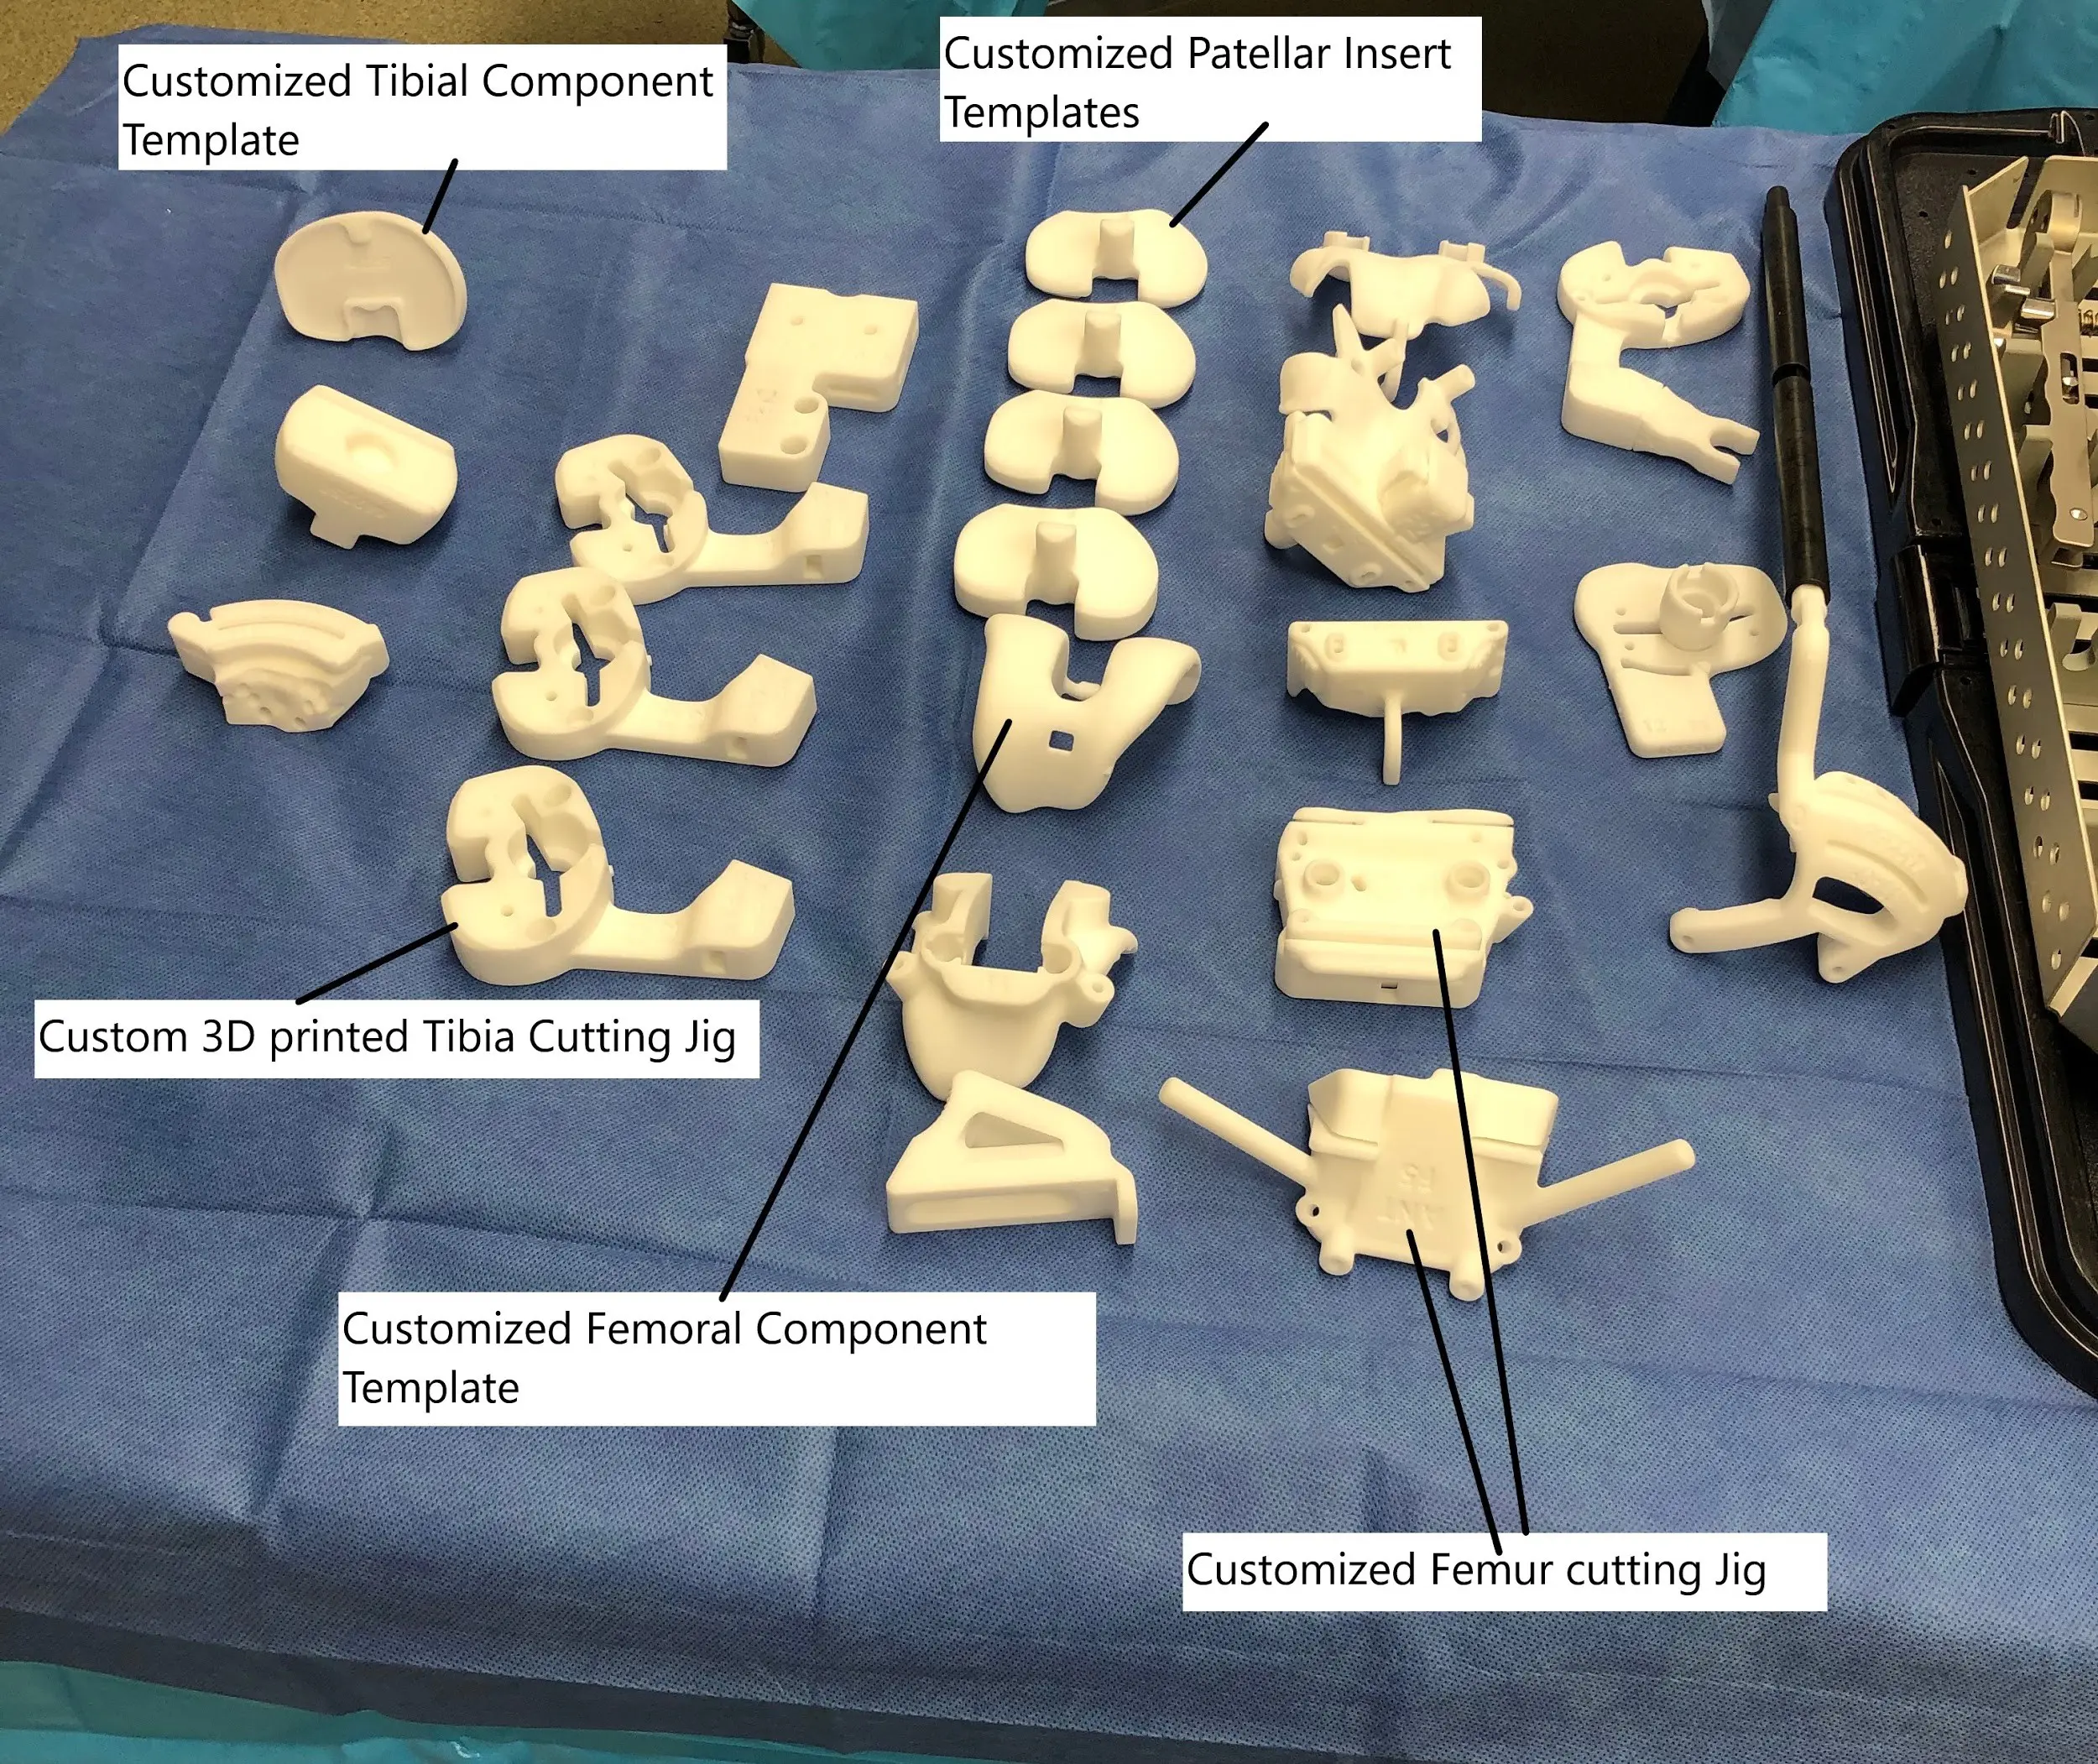

Custom 3D printed cutting blocks.

The data is then used to create patient-specific cutting blocks to minimize bone loss and ensure accurate placement of the customized implants. The result is a more kinematic knee and patients may experience a more natural-feeling knee joint.

Another system utilizes customized instruments/cutting blocks without custom-made implants. The patient’s knee CT/MRI images are used to create 3D anatomy and assess the mechanics of the patient’s knees. The resulting cutting blocks are used to make accurate bone cuts and minimize bone loss. The implants used are off-the-shelf implants.

Customized cutting blocks, also known as patient-specific instrumentation (PSI), involve creating surgical guides tailored to the patient’s knee anatomy. Like customized implants, this process begins with detailed imaging of the knee. The 3D model generated from these images is used to design cutting blocks that guide the surgeon in making precise bone cuts. The actual implants used can still be standard sizes, but the bone preparation is more tailored to the patient’s anatomy.